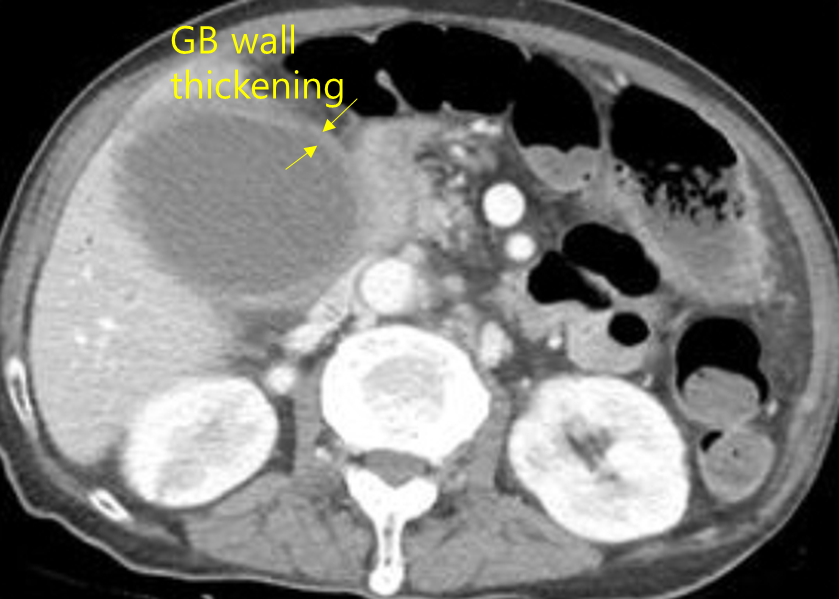

88세 여자가 2일 전부터 명치가 아프고 1일 전부터 열이 나서 응급실에 왔다. 3년 전 뇌경색 발생 이후 거동이 불가하여 요양병원에서 누워서 생활하고 있다고 한다. 혈압 80/50 mmHg, 맥박 110회/분, 호흡 26회/분, 체온 38.9℃이다. 오른쪽 윗배에 압통이 있다. 혈액검사 결과는 다음과 같다. 복부 컴퓨터단층촬영 사진이다. 치료는?

Img | CT: GB distension, GB wall thickening |

RUQ dT(+), WBC/CRP elevation, CT상 GB inflammation 소견으로 보아 급성 담낭염 진단 하, 환자의 상태가 불안정하나 즉각적 수술이 어려운 상황이므로 우선 PTGBD를 시행한다.

• WBC와 CRP의 상승으로 보아 감염에 의한 급성 염증의 증거가 있으며, CT상 GB distension과 GB wall thickening 등 급성 담낭염의 소견이 보인다.

진단 | • US(1st line), CT: GB stone, GB wall thickening, pericholecystic fluid |